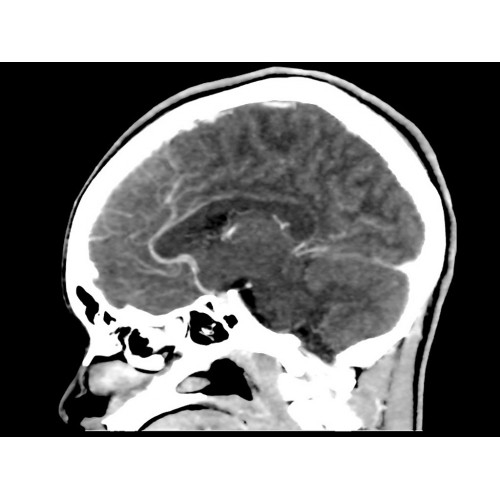

Современный КТ аппарат GE Optima CT520 – это инновационное оборудование для точной и быстрой диагностики. Он сочетает в себе передовые технологии, надежность и удобство использования, что делает его востребованным в медицинских учреждениях различного профиля.

• Широкая область применения: от неврологии до кардиологии и онкологии.

Неврологические исследования

• Выявление инсультов, опухолей головного мозга и травматических повреждений.

• Диагностика заболеваний позвоночника и межпозвоночных грыж.